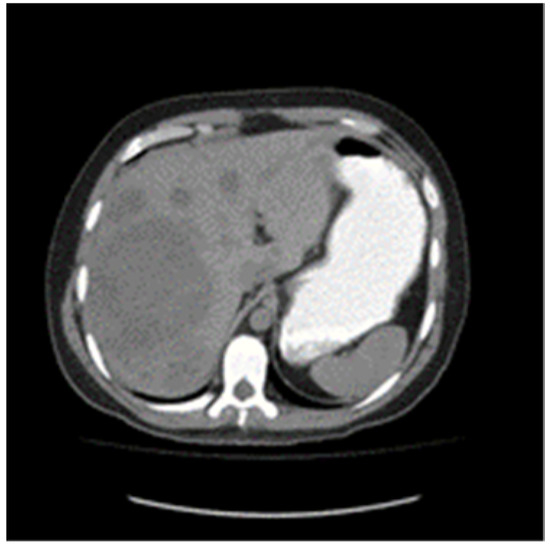

Nineteen months from diagnosis, the largest liver lesion demonstrated growth on imaging; however, tumor markers remained normal (Figure 3). Resection of this large lesion in segment 7, as well as a wedge resection of a smaller lesion in segment 8, was performed. Pathology revealed mature teratoma in both the 5.5 cm and 0.8 cm lesions.

Figure 3. From left to right, Post-chemotherapy unenhanced CT Scan showing improvement in liver metastases and 18 month follow up enhanced CT scan showing enlarging dominant liver metastases.